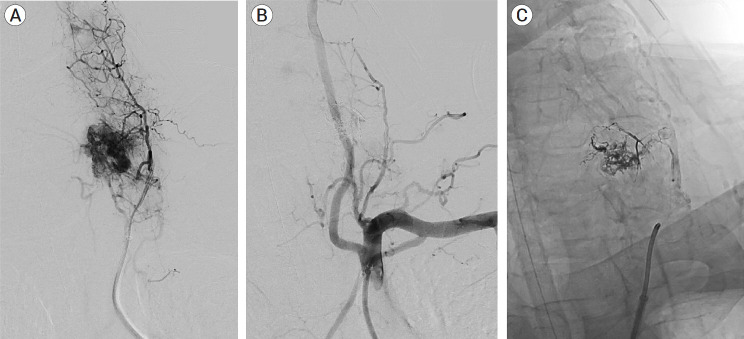

这是一例独特的颈椎转移性嗜铬细胞瘤病例,患者在术前接受了栓塞治疗,随后进行了全切。一名 65 岁的男性患者患有转移性嗜铬细胞瘤,两周前出现颈部疼痛加重、左臂和左腿无力和麻痹以及尿失禁。磁共振成像显示,C6 处有转移性骨质病变,并伴有严重狭窄和脊髓压迫。患者术前使用液体栓塞剂成功进行了血管栓塞,随后进行了C5-C7椎板切除术、肿瘤全切术和C3-T2后路脊柱融合术。术后六周,患者表示体力有所改善,颈部疼痛和麻痹症状也得到了缓解。虽然目前还没有治疗颈椎转移性嗜铬细胞瘤的标准范例,但术前栓塞可以最大限度地减少术中失血和随后手术切除时血流动力学的不稳定。

This is a unique case of metastatic pheochromocytoma of the cervical spine treated with preoperative embolization and subsequent en bloc resection. A 65-year-old man with metastatic pheochromocytoma presented with two weeks of worsening neck pain, left arm and leg weakness and paresthesia, and urinary incontinence. Magnetic resonance imaging showed a metastatic osseous lesion at C6 with severe stenosis and spinal cord compression. The patient underwent successful preoperative angiographic embolization with a liquid embolic agent followed by C5-C7 laminectomy, en bloc tumor resection, and C3-T2 posterior spinal fusion. Six weeks postoperatively, the patient reported improving strength and resolving neck pain and paresthesias. While there is no standard paradigm for the treatment of metastatic pheochromocytomas of the cervical spine, preoperative embolization may minimize intraoperative blood loss and hemodynamic instability during subsequent surgical resection.